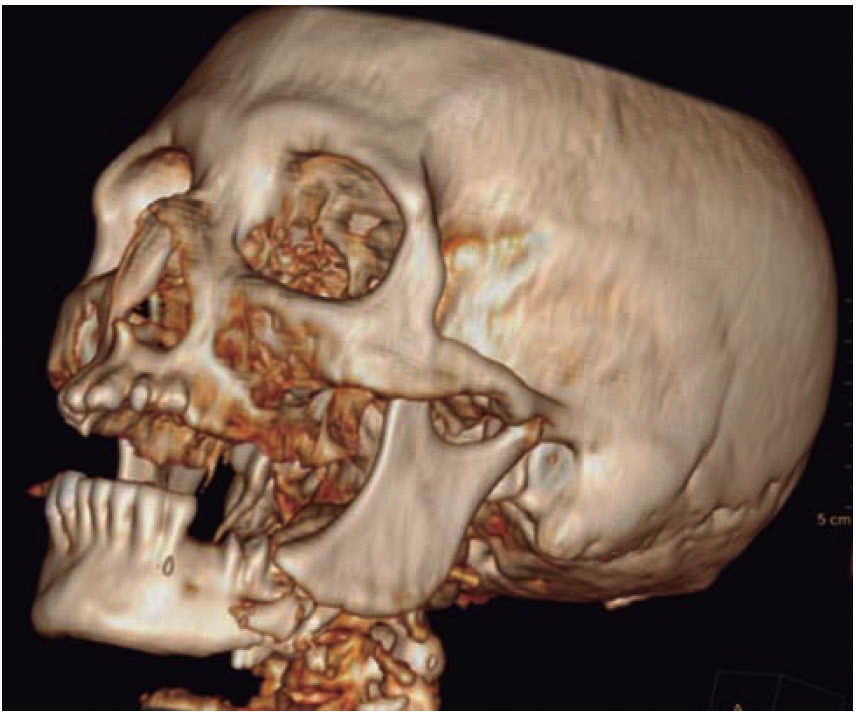

Clinical case 3

A 73 year old female with diagnosis of fracture of left mandibular body due to firearm projectile (Figure 12). The patient informed she was assaulted in the street, and upon offering resistance to the theft of her vehicle, she was shot at a distance of two meters. She arrived at our institution eigt days after the assault, having previously been treated in another hospital. Physical exploration revealed hyperemic area and volume increase in fluctuating left submandibular region; entry orifice at left submandibular level with presence of fetid whitish secretion and closed exit wound at right cervical level. Intraoral examination revealed partial edentulism, with multiple maxillary septic foci, and at the left mandibular fornix, a root remnant of the first molar in the fracture line as well as accentuated mobility of the mandibular segment caused by fracture which hindered deglutition.